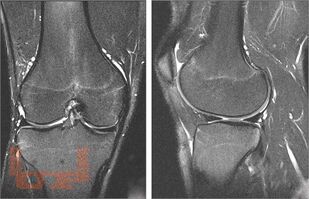

В методических рекомендациях рассмотрены вопросы выполнения шва мениска при его повреждении. Представлена МРТ-диагностика повреждений менисков, артроскопическая классификация разрывов, определены показания и противопоказания к хирургическому лечению, необходимое обеспечение, представлены алгоритм принятия решения, актуальные хирургические техники, реабилитационное лечение. Пособие предназначено для слушателей послевузовского и дополнительного образования, травматологов-ортопедов, занимающихся артроскопическими вмешательствами на коленном суставе.